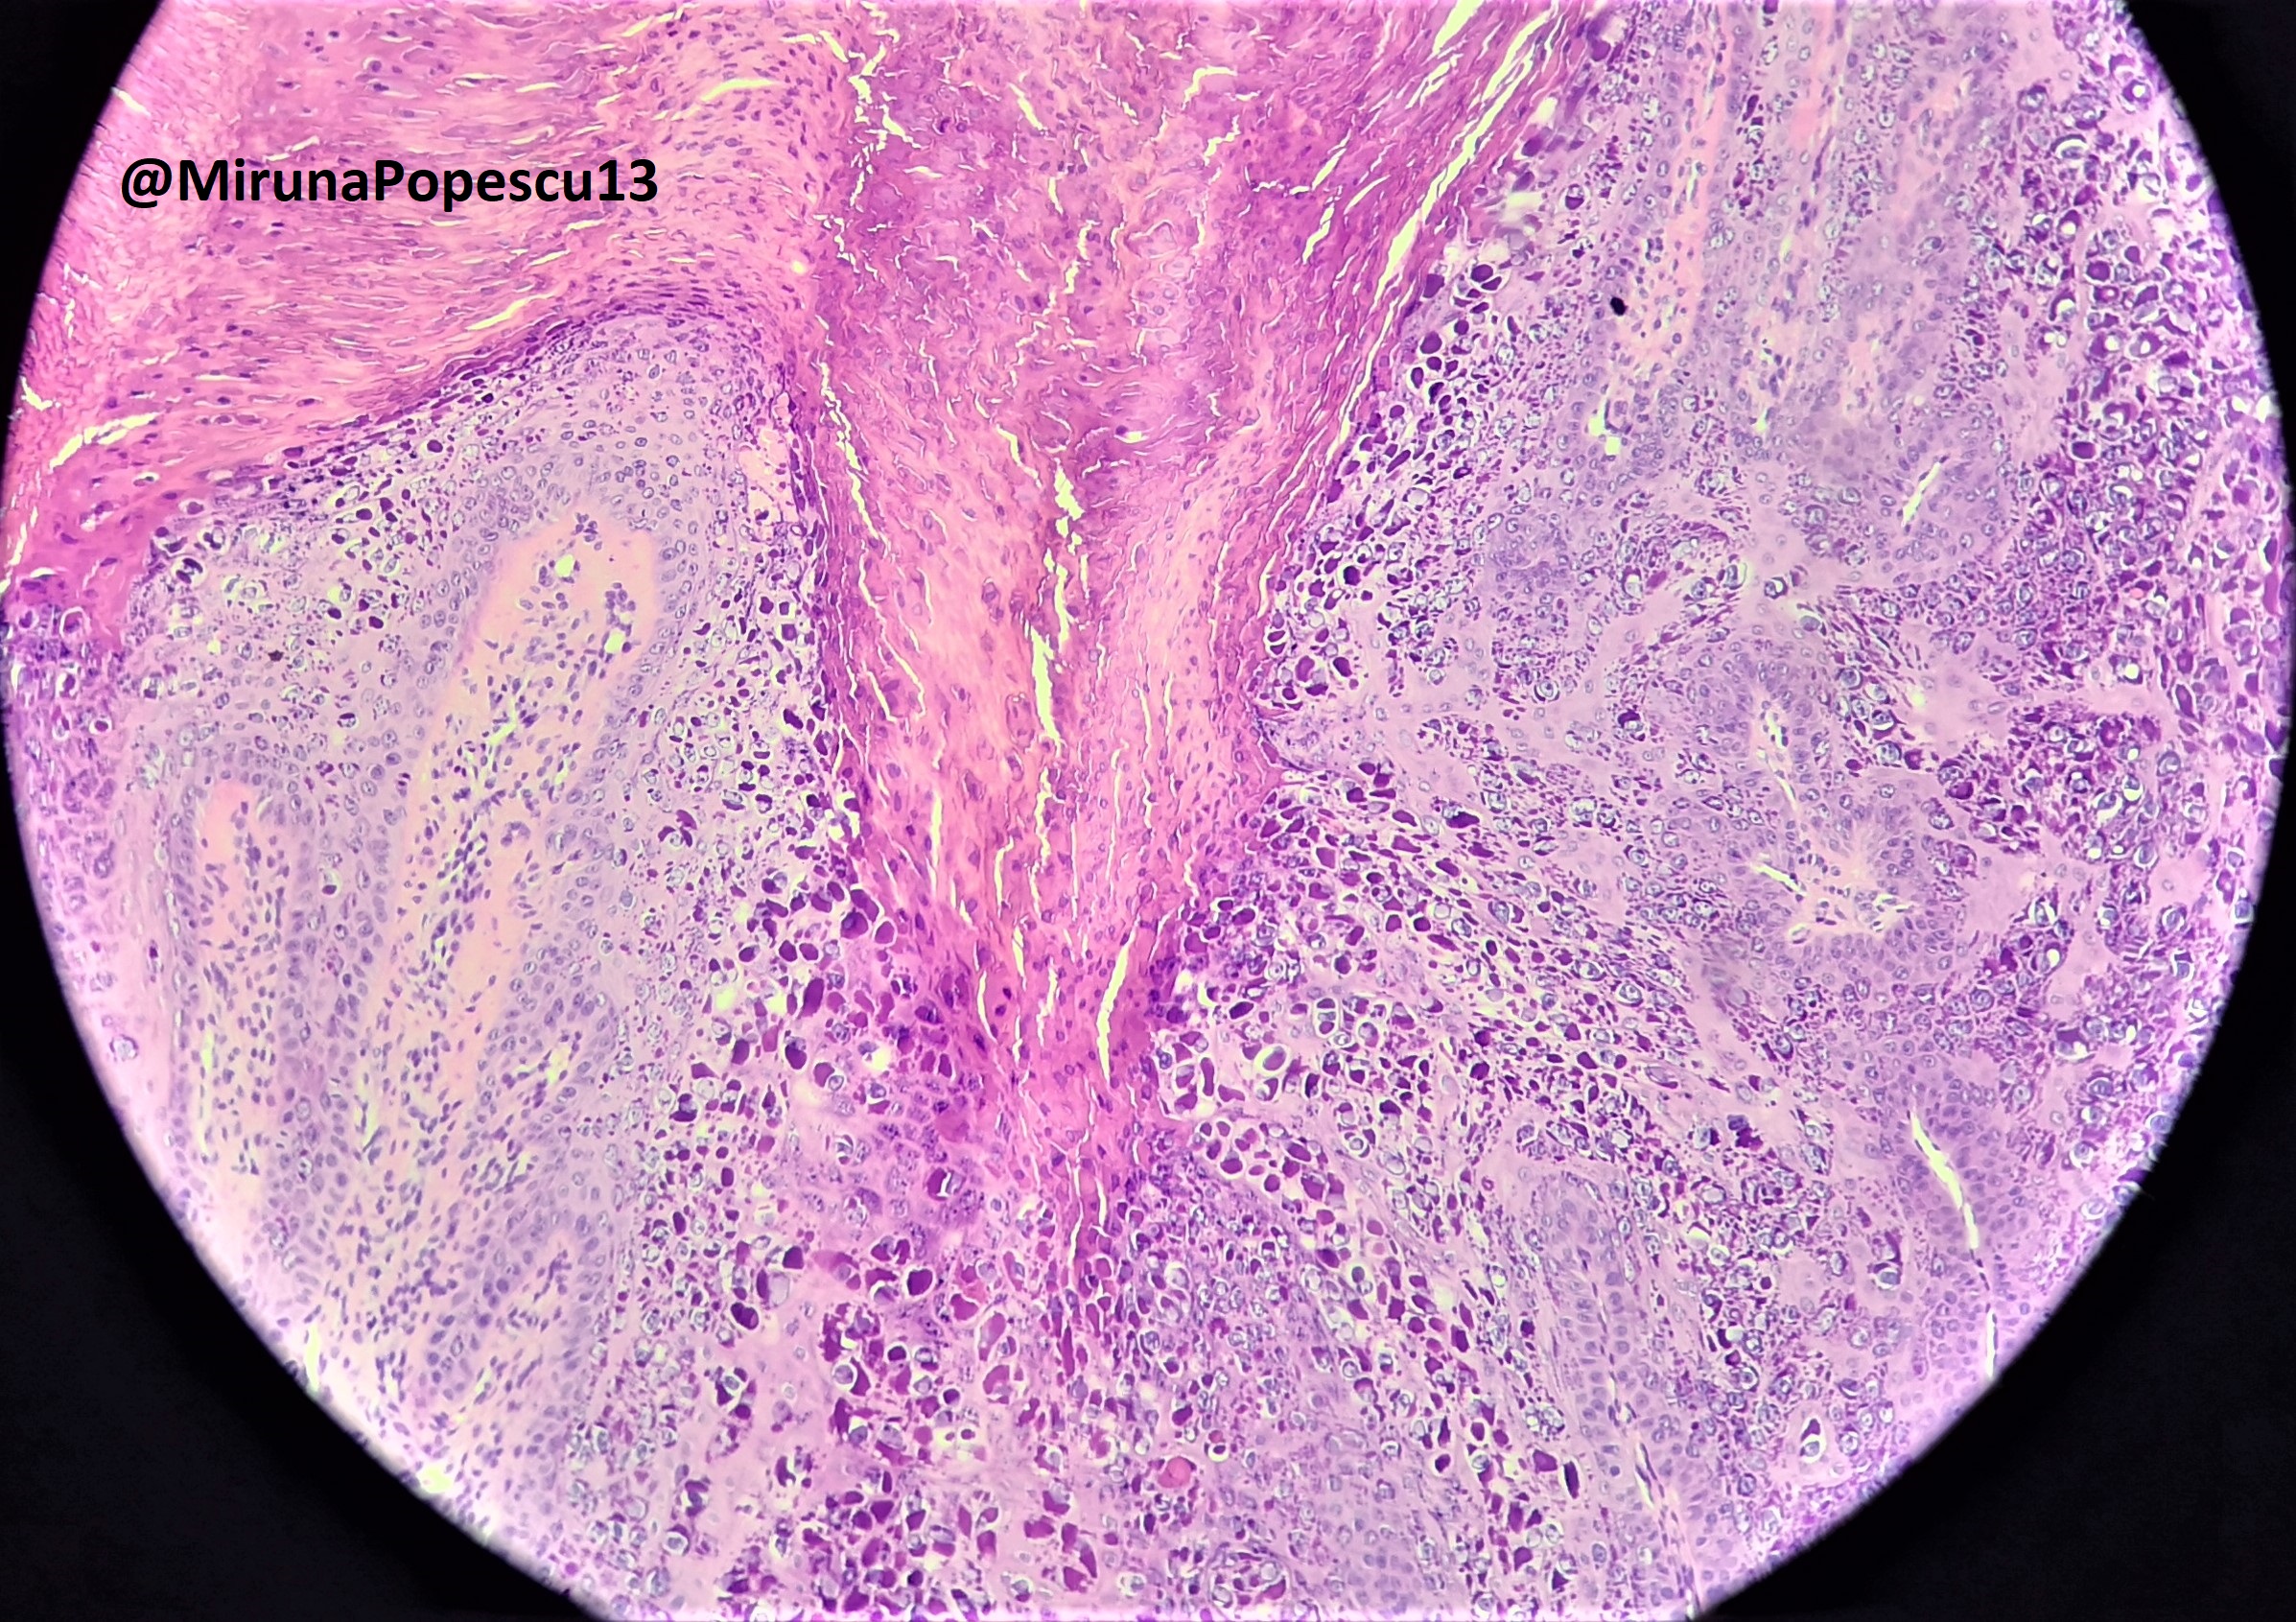

Microscopic (histologic) description

- Common warts (verruca vulgaris) (Arch Pathol Lab Med 2018;142:700):

- Hyperkeratosis, papillomatosis, hypergranulosis

- Columns of parakeratosis, especially over projecting dermal papillae

- Intracorneal hemorrhage

- Vacuolated superficial keratinocytes with pyknotic raisin-like nuclei (koilocytes)

- Koilocytes may not be seen in older lesions

- Koilocytes are not needed for the diagnosis

- Inward bending of rete ridges at borders of lesion (toeing in)

- Dilated capillaries in dermal papillae

- Projects above the plane of the epidermis

Microscopic (histologic) images

Contributed by Heba Ahmed Abdelkader, M.D., Hillary Rose Elwood, M.D., AFIP,

@MirunaPopescu13 on Twitter and @shilpa_rakesh_path on Instagram